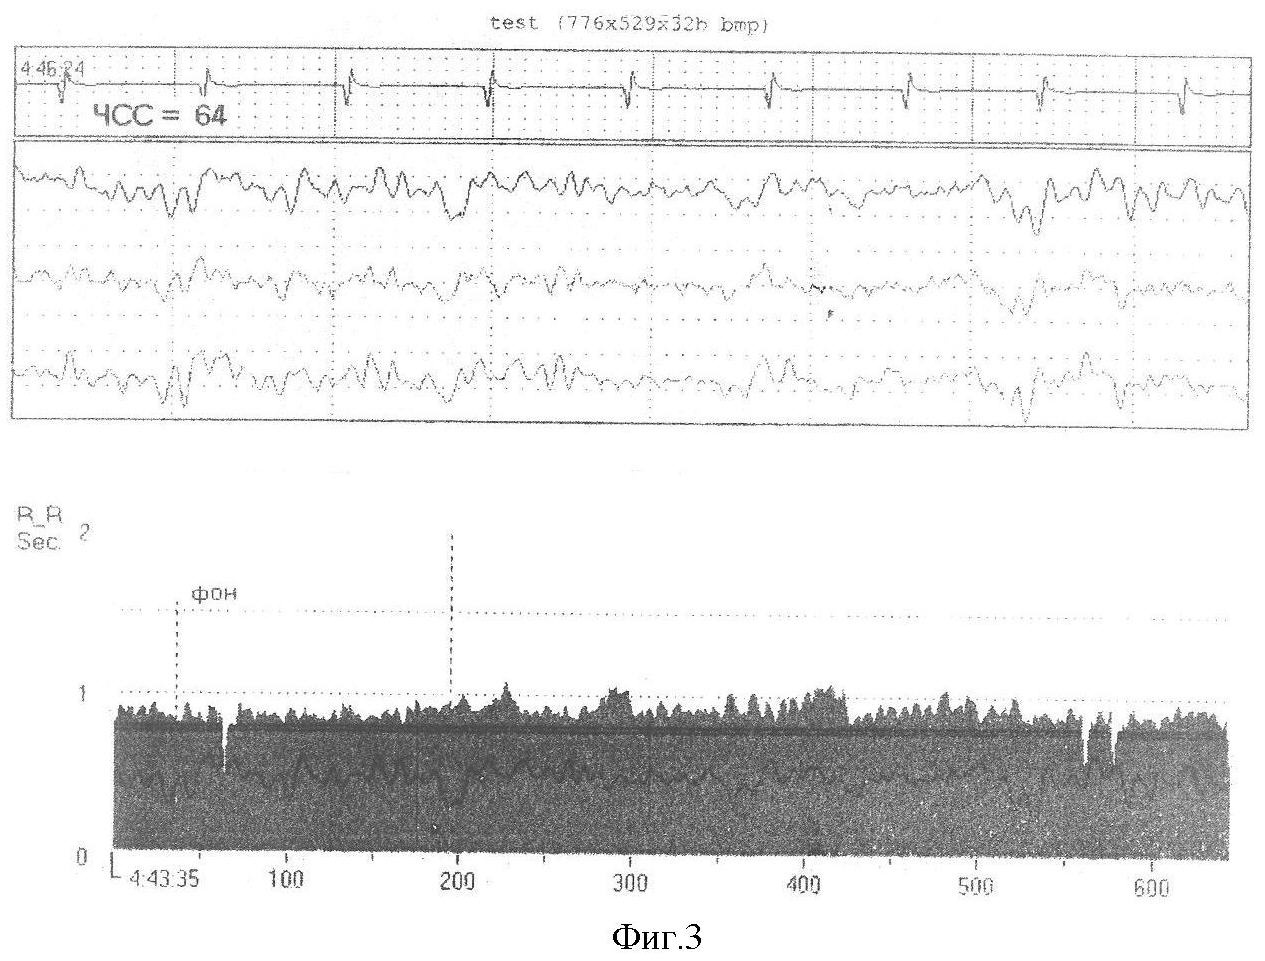

Сущность изобретения поясняется чертежами, где на фиг.1 изображена схема введения электрода, на фиг.2 изображено устройство для регистрации биопотенциалов головного мозга, на фиг.3 – электроэнцефалограмма.

Проводим пример-выписку из истории болезни. Больной П., 42 лет, и/б 1893-2006, около 5 лет беспокоят генерализованные судорожные припадки с потерей сознания, до 6-7 припадков в месяц. Выполнено КТ исследование головного мозга, при котором заподозрено объемное образование головного мозга в правой теменной и височной доли. Выполнена ангиография сосудов мозга, обнаружена АВМ правой теменной и височной доли. При ЭЭГ диагностике эпилептического очага не обнаружено. Согласно заявляемому способу выполнена ЭЭГ диагностика эндоваскулярным микроэлектродом. Пропунктирована правая бедренная артерия, установлен интрадюсер, через который заведен катетер, в катетер заведен микрокатетер с микроэлектродом, записали биопотенциалы головного мозга из правой средней мозговой и правой передней мозговой артерии, при этом удалось идентифицировать эпилептический очаг, который локализовался в медиальных отделах правой височной доли. На фиг.3 представлены данные ЭЭГ. Была подобрана противосудорожная терапия, на фоне которой отмечается регресс эпилептических припадков, послеоперационных осложнений не наблюдалось. У больного в течение одного года припадков не было.